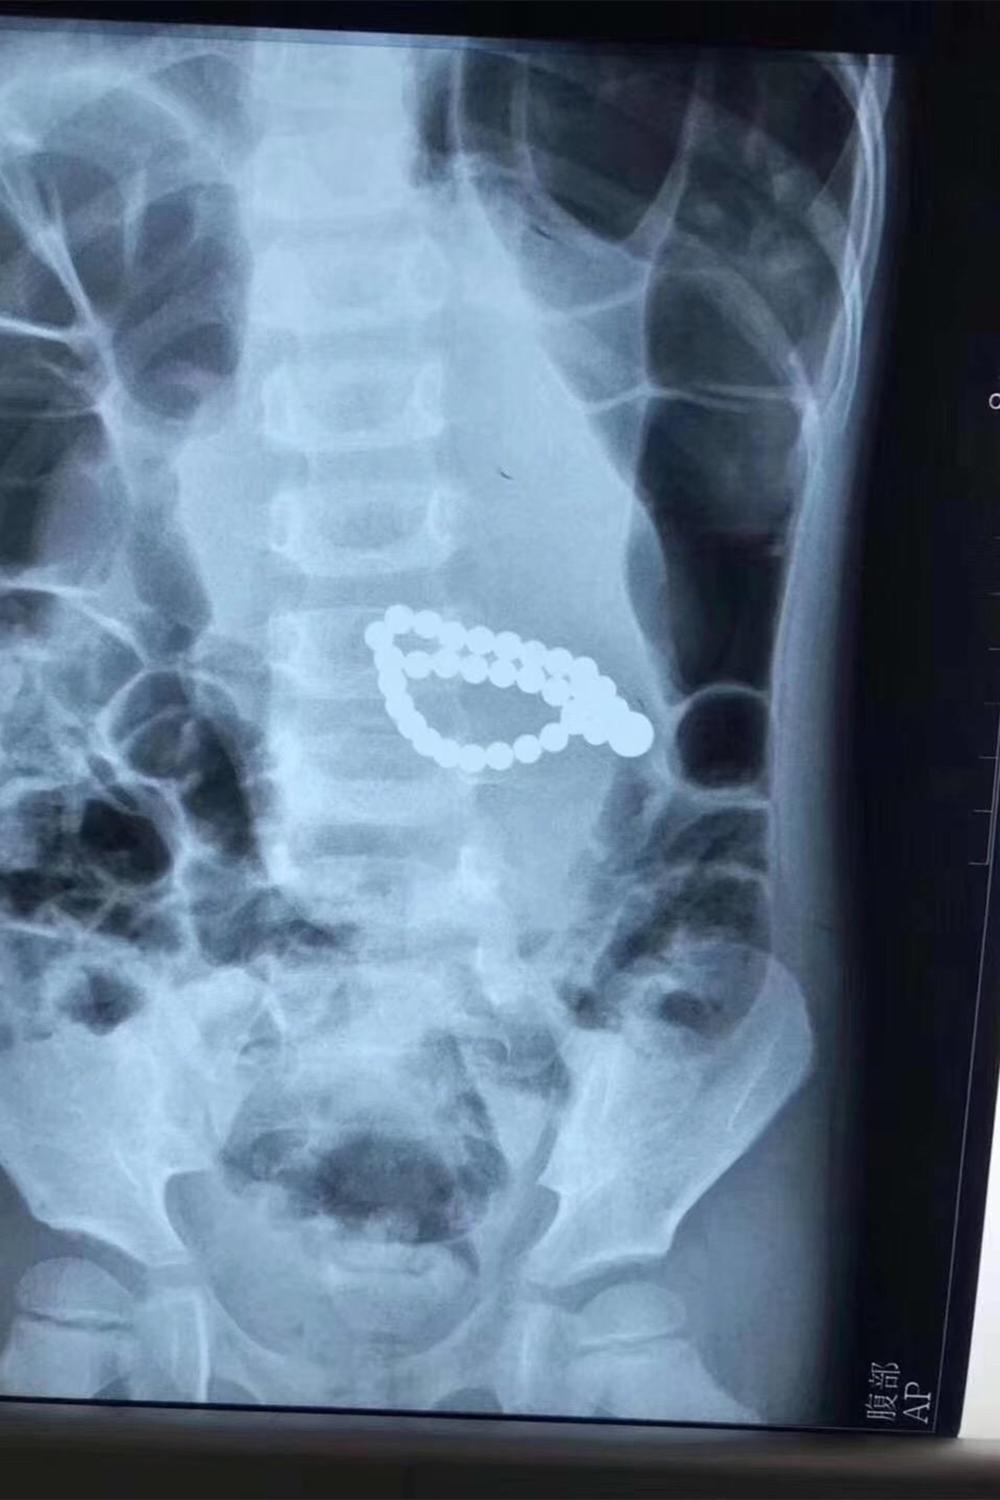

之前好多玩具都被曝光过对儿童危害极大,其中又以被央视曝光过的3款为最,分别是磁力珠(巴克球)、水晶泥(史莱姆)和激光笔。

这3种玩具无一例外都造成过数起悲剧,比如误吞磁力珠导致肠胃受损的、水晶泥中含有硼砂导致孩子中毒的以及激光笔伤到儿童眼睛的。类似的玩具家长一定不要再给孩子选择了。